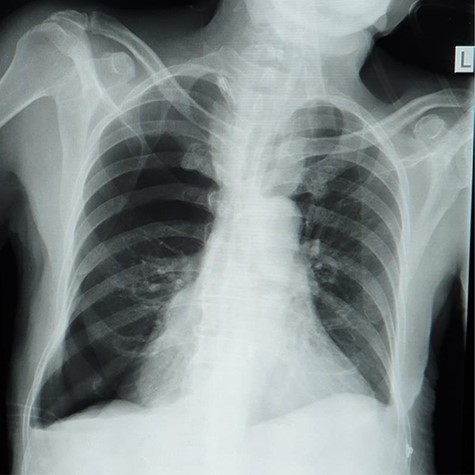

Radiological findings

An abdominal ultrasound showed a mass in the posterior wall of the urinary bladder measuring 6 cm × 7 cm with areas of necrosis. There was left moderate ureter hydronephrosis. The right kidney and the rest visceral organs were normal. Chest X-ray revealed multiple macronodules all over the lung fields. Heart size, costophrenic and cardiophrenic angles were all normal (Fig. 6).

The final diagnosis of metastatic adenocarcinoma of the urinary bladder was made and the patient was referred for palliative radiation therapy.